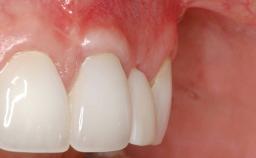

A 30-year-old woman was referred by her general dentist for evaluation of an esthetic complication related to previous implant treatment for congenitally missing maxillary lateral incisors. The patient’s chief complaint was the inadequate esthetic appearance of her smile. The case demonstrates the use of a combined approach to achieve optimal results. Two different flap designs - a tunnel technique and a coronally advanced flap - are employed based on the surgical objectives for the affected site.

Soft Tissue Grafting Yes

Soft Tissue Anatomy Intact Defective